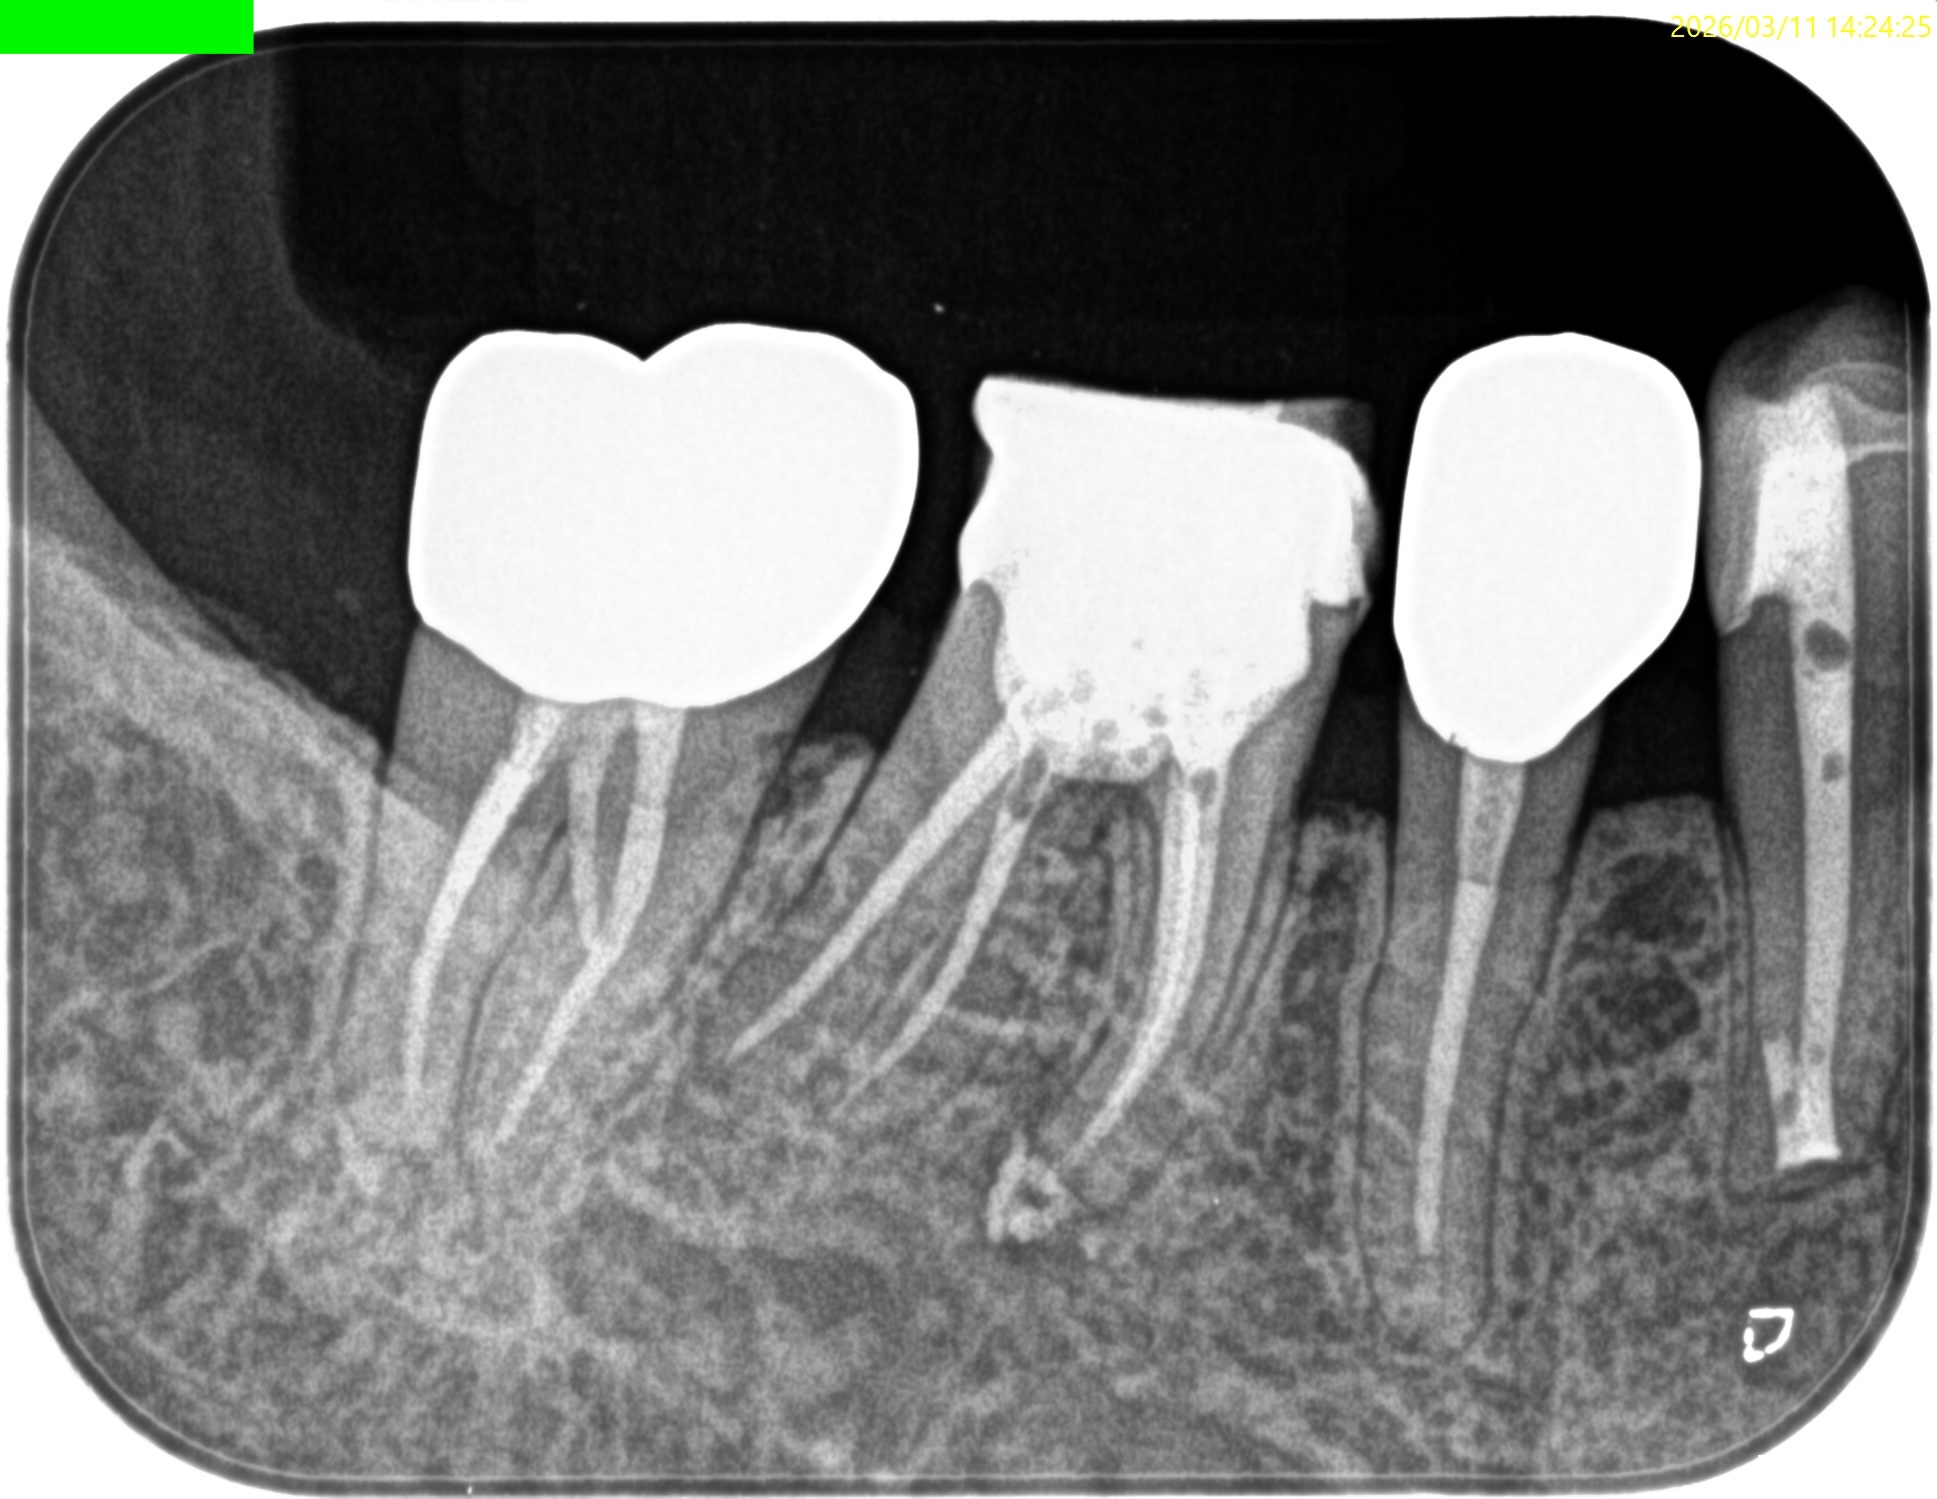

Pre-op Endo test(2026.3.11)

MB

ML

D

Radix

Gold Inlayの封鎖性を持ってしても歯髄の生活性を担保することはできなかったようだ。

ということでRadix以外の根管全てに根尖病変があり、穿通がマストだ。

が、歯髄に近い修復で石灰化が進んでいる。

Pulp Dx: Pulp Necrosis

Periapical Dx: Symptomatic apical periodontitis

Recommended Tx: RCT